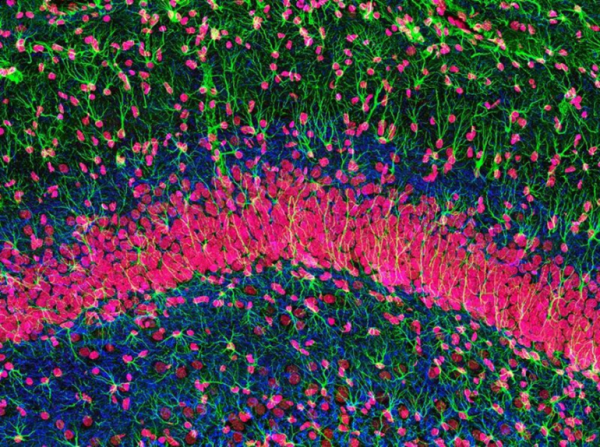

一般而言,哺乳动物成年后神经发生主要集中在两个区域:负责学习和记忆的海马体和负责嗅觉的嗅球(图7),神经发生的研究也主要针对这个区域。大脑素有人体“紫禁城”之称,“紫禁城”内的神经系统拥有数量巨大的神经元,具有复杂的网络结构,神经元之间的连接也更趋复杂和多样,这无疑为神经发生研究带来巨大挑战。

图7 海马区的神经元(红色)(图源:Thomas Deerinck)